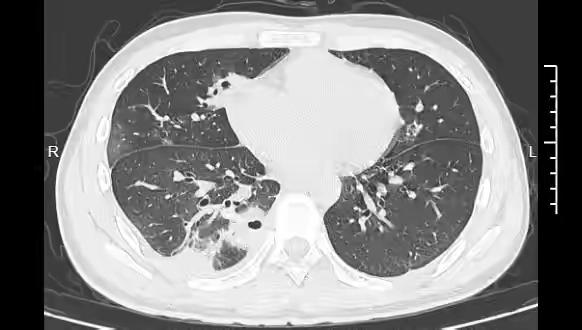

手贱挤颗痘,肺被啃出10多个洞!20岁小伙差点救命 谁能想到,挤颗痘痘能把肺搞出“蜂窝煤”?宁波这位20岁大学生的经历,简直是现实版“祸从手出”! 大二学生小林熬夜备考,脸上冒了颗黄豆大的痘痘,没洗手就随手挤了,当时还觉得神清气爽。结果没几天,他就发烧咳嗽,退烧药不管用,胸口疼得像被针扎,烧到39℃才赶紧去宁波大学附属第一医院。CT一查吓傻众人,肺里竟有10多个空洞,部分肺都坏死了,确诊是血源性肺脓肿。 原来痘痘长在脸部“危险三角区”,这地方的血管没“防护门”,挤压的细菌顺着血液跑到了肺部。好在小林年轻扛得住,12天抗生素治疗才捡回一条命。老话常说“小洞不补,大洞吃苦”,这痘痘就是典型! 别觉得挤痘是小事,“危险三角区”的痘痘挤不好可能引发脑膜炎,甚至危及生命。皮肤自己会修复,没必要瞎折腾。咱们可得管住手,不然小毛病闹出大危险,真就得不偿失啦!痘痘 粉刺爆痘